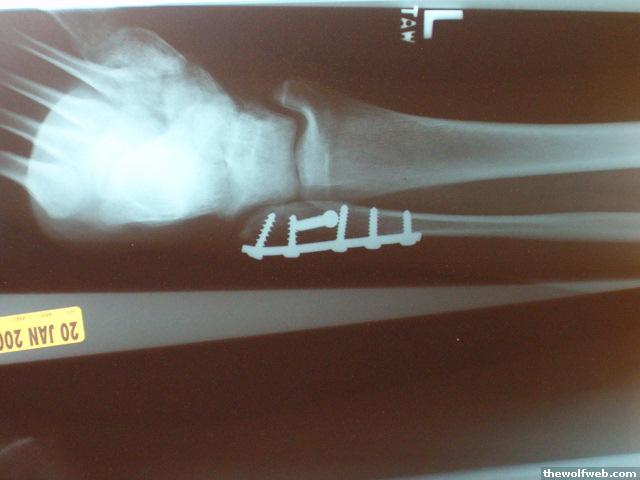

Photo Gallery » brookeb25 » my ankle!

my ankle!